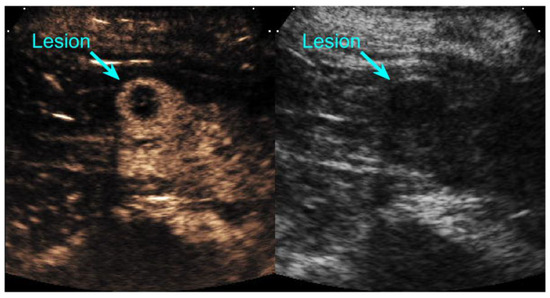

2.2. Imaging Protocol

2.3. Image Preparation and Reader Interpretation